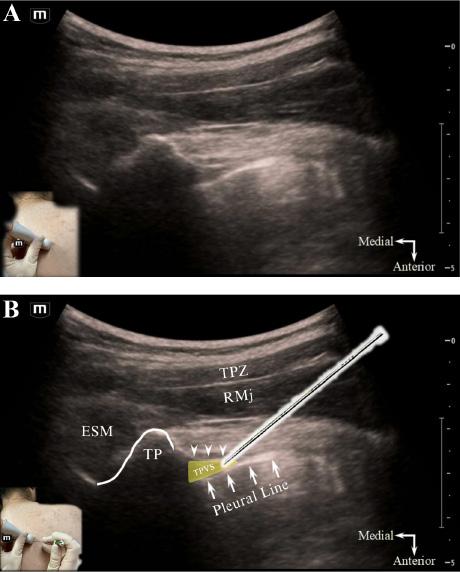

334 Thoracic Paravertebral Block for Tube Thoracostomy Analgesia in the Emergency Department: A Case Report

MT Reeves